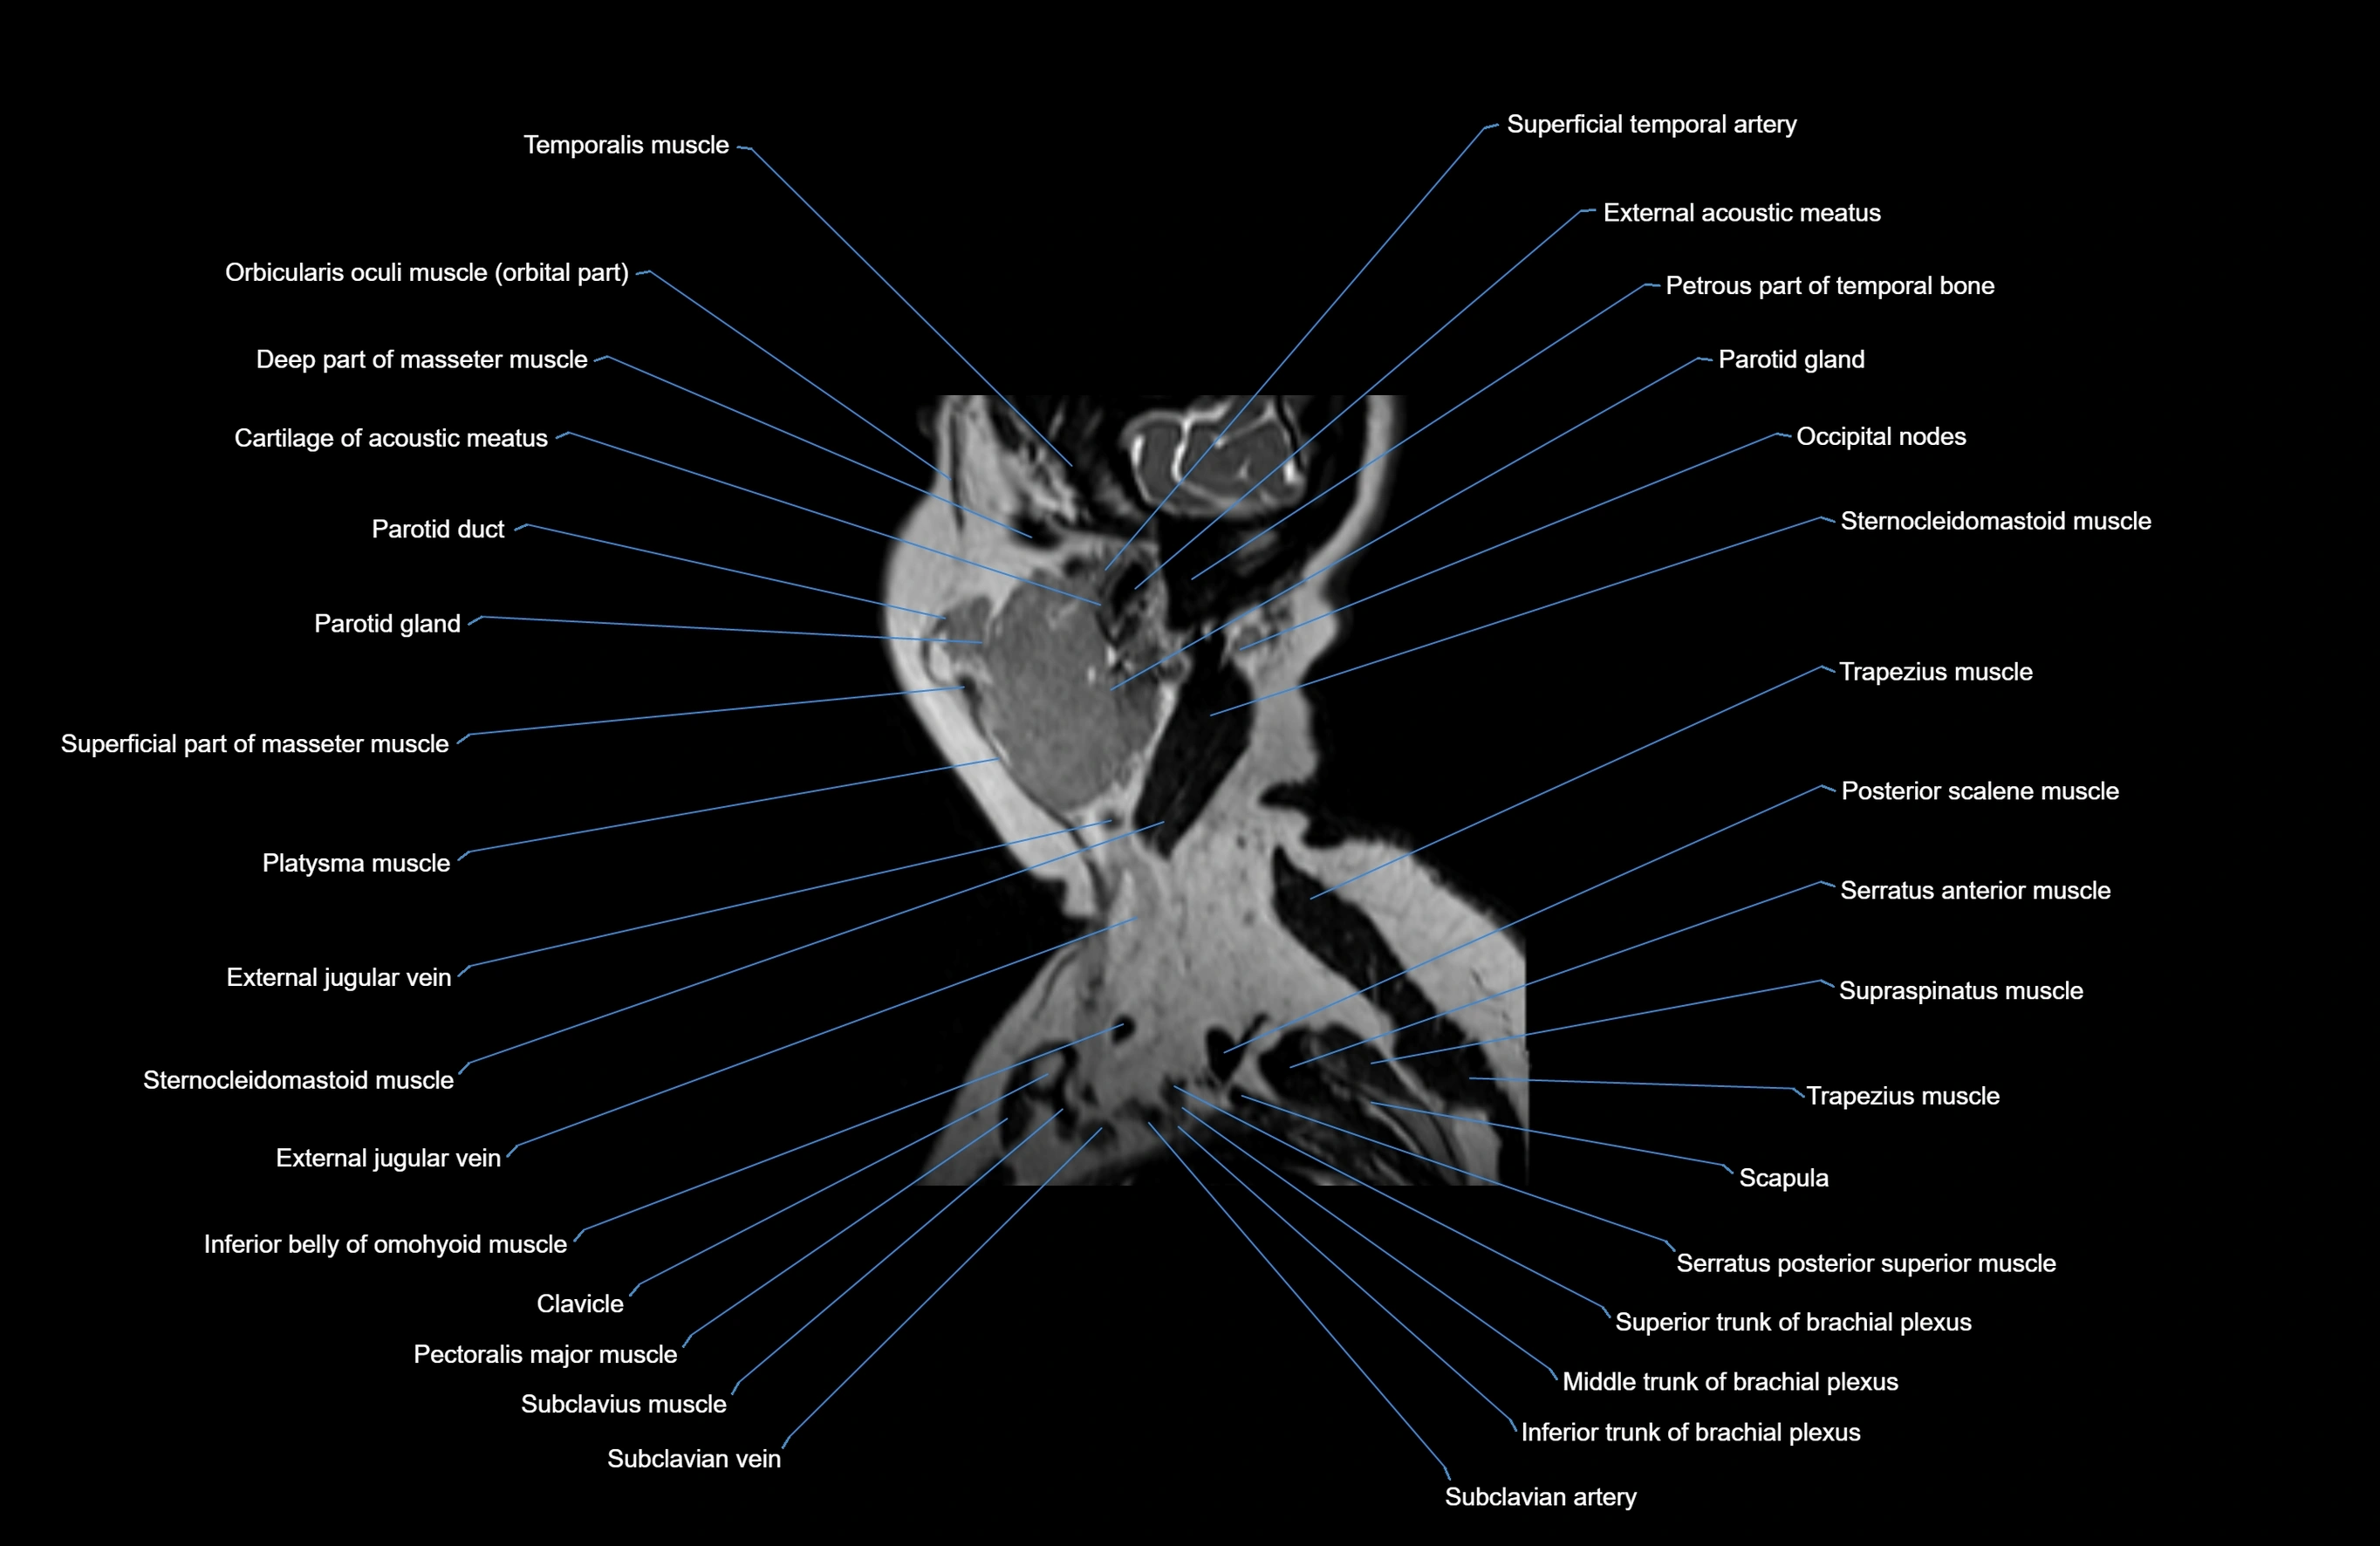

MRI images